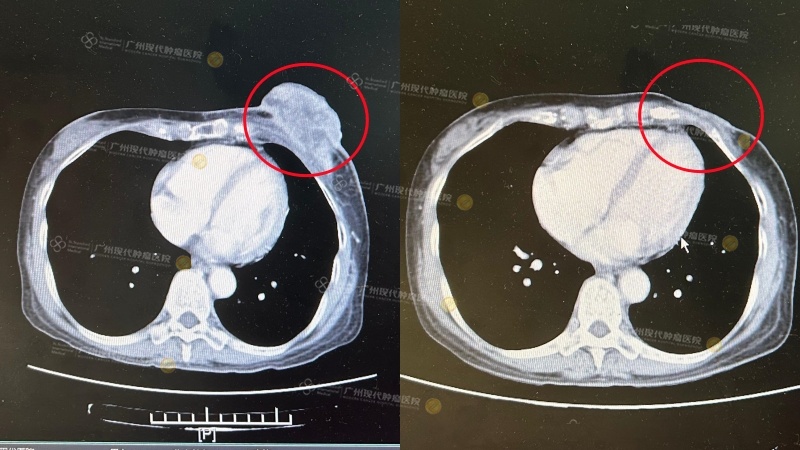

หลังจากที่เธอเข้ารับการรักษาในโรงพยาบาล เธอได้รับการตรวจ CT อย่างละเอียด พบว่ามะเร็งที่เต้านมด้านซ้ายลามมาบนผิวหนังและกล้ามเนื้อหน้าอกด้านซ้าย ผลตรวจทางพยาธิวิทยาเผยว่าเป็นมะเร็งเต้านมแบบลุกลามออกนอกท่อน้ำนมขนาด 37*68 มม. ทีมแพทย์ MDT ของโรงพยาบาลมะเร็งสมัยใหม่สแตมฟอร์ดกว่างโจว ได้ประเมินอาการของเธอและวางแผนการรักษาด้วยการจี้ผ่านคลื่นไมโครเวฟ + การคีโมเฉพาะจุดผ่านหลอดเลือดแดงให้แก่เธอ

แปดวันต่อมา เธอเข้ารับการคีโมผ่านหลอดเลือดแดง ด้วยการฉีดยาชาเฉพาะจุด ภายในเดือนกรกฎาคม พ.ศ. 2567 เธอได้รับการจี้ด้วยไมโครเวฟ 1 ครั้ง และการคีโมเฉพาะจุด 6 ครั้ง อาการของเธอดีขึ้นอย่างเห็นได้ชัด ผล CT ของเธอในเดือนมิถุนายนแสดงให้เห็นว่าก้อนมะเร็งเล็กลงเหลือ 16 มม.*28 มม.

12 มีนาคม 2567 19 มิถุนายน 2567